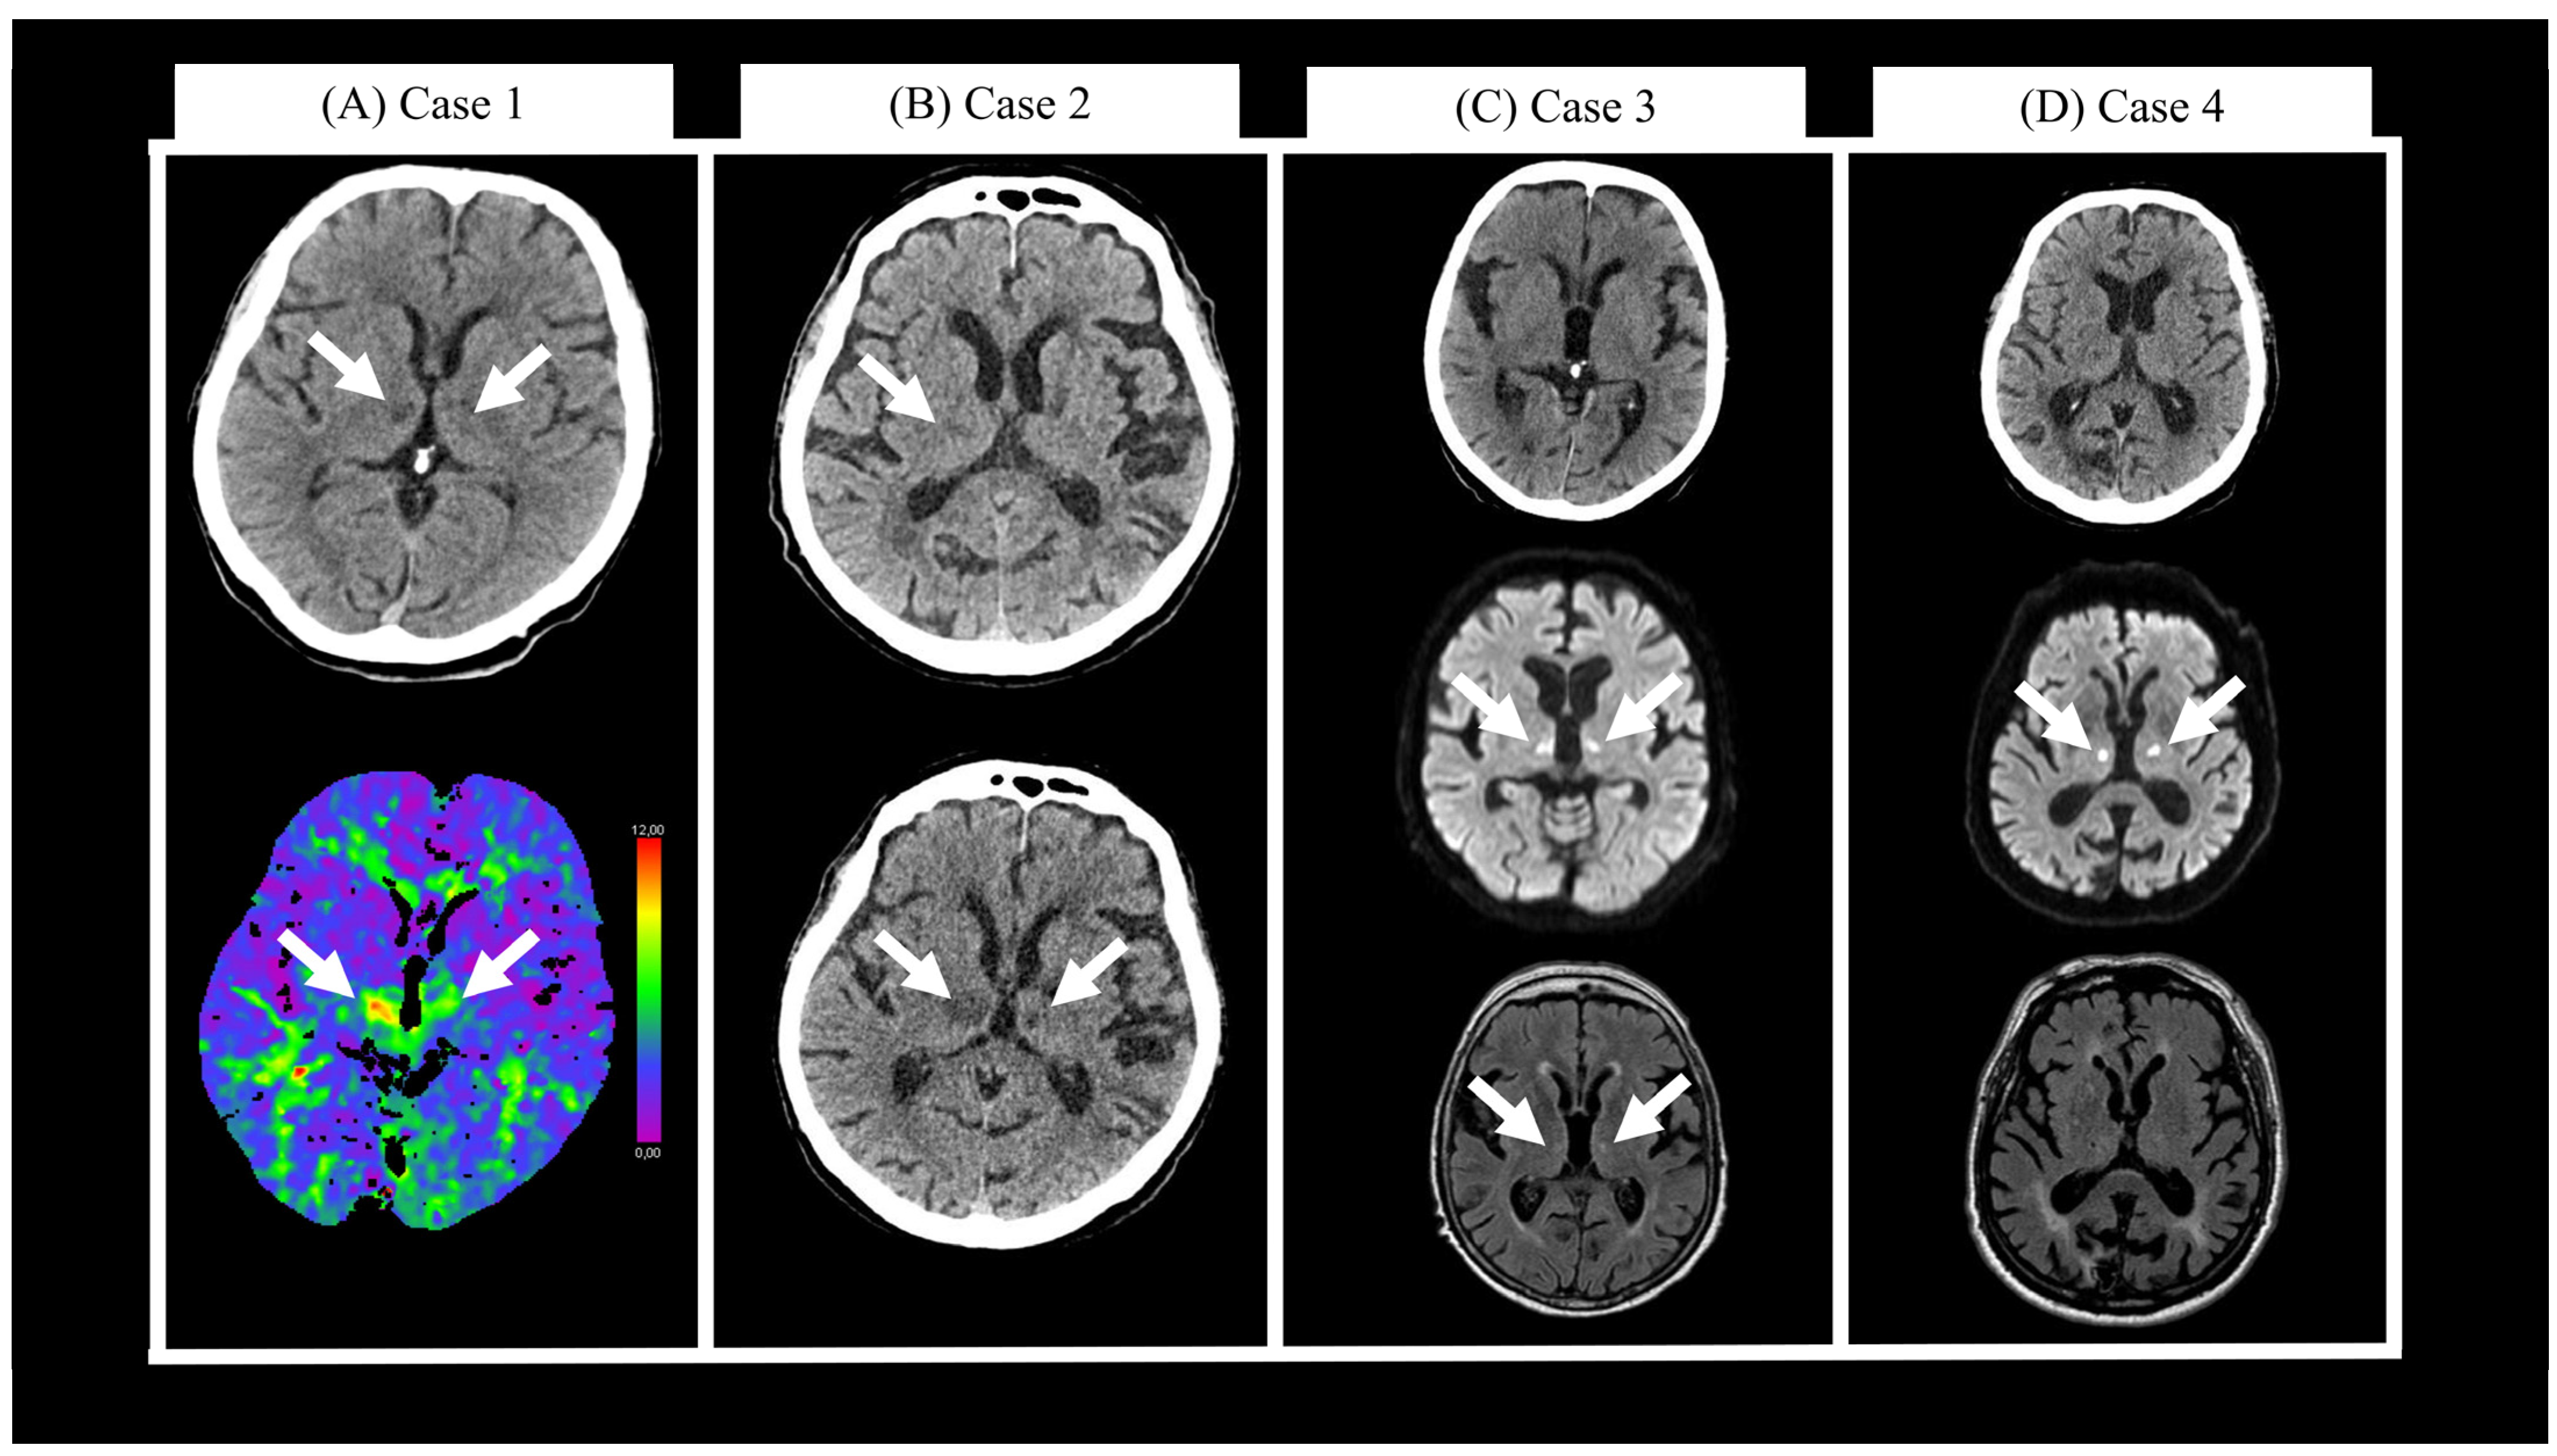

2.1. Case 1

2.2. Case 2

2.3. Case 3

2.4. Case 4